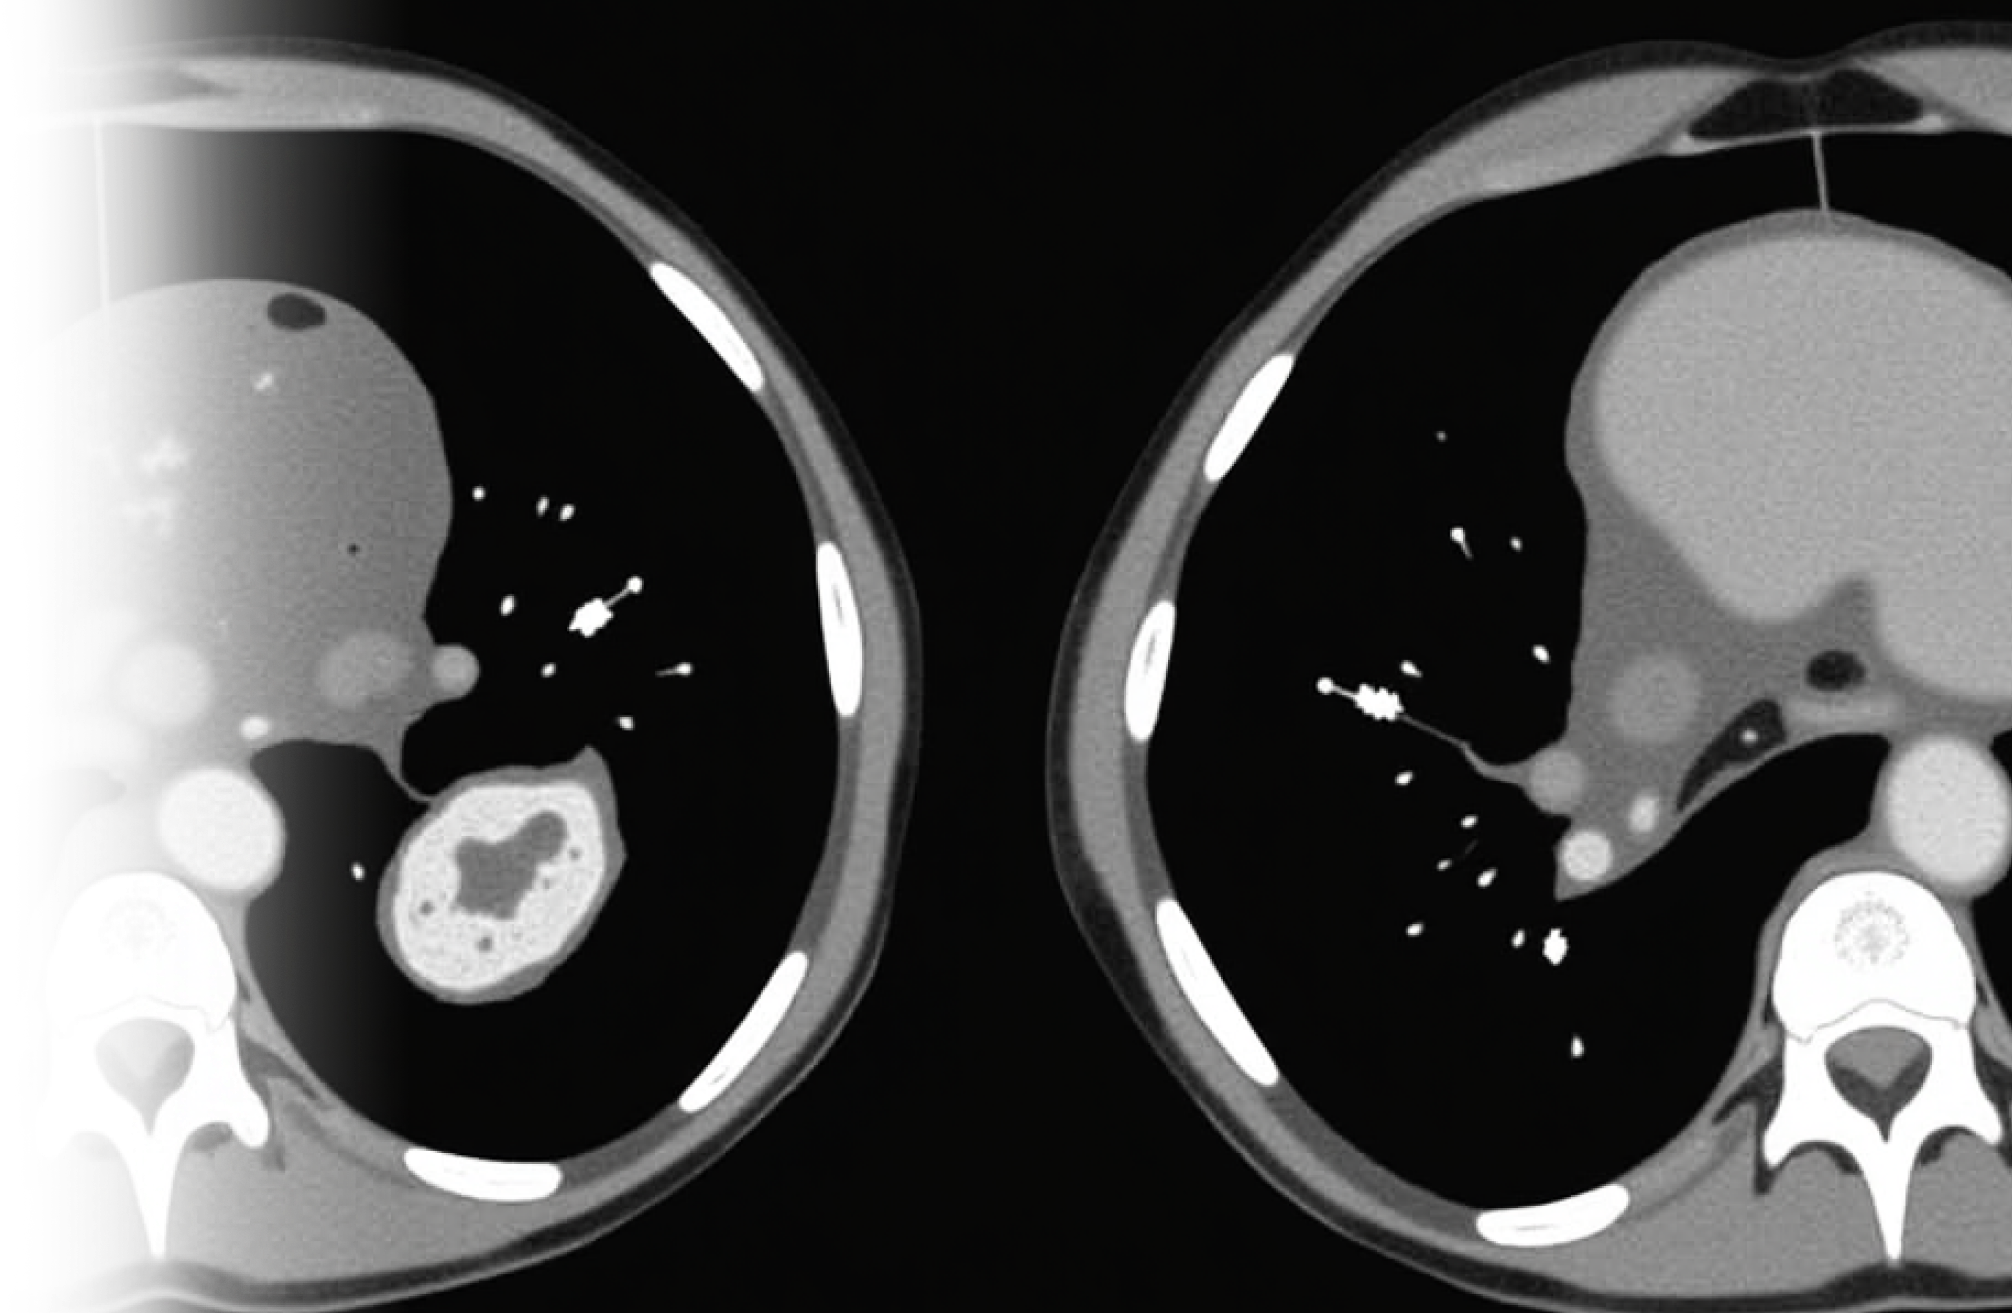

Компьютерная томография брюшной полости и забрюшинного пространства – важный метод исследования органов брюшной полости и забрюшинного пространства без введения контрастного препарата.

Для любой из вышеописанных патологий органов брюшной полости целесообразно внутривенное введение контрастного препарата за исключением узких диагностических задач.

Исследование почти всегда проводится с внутривенным контрастированием